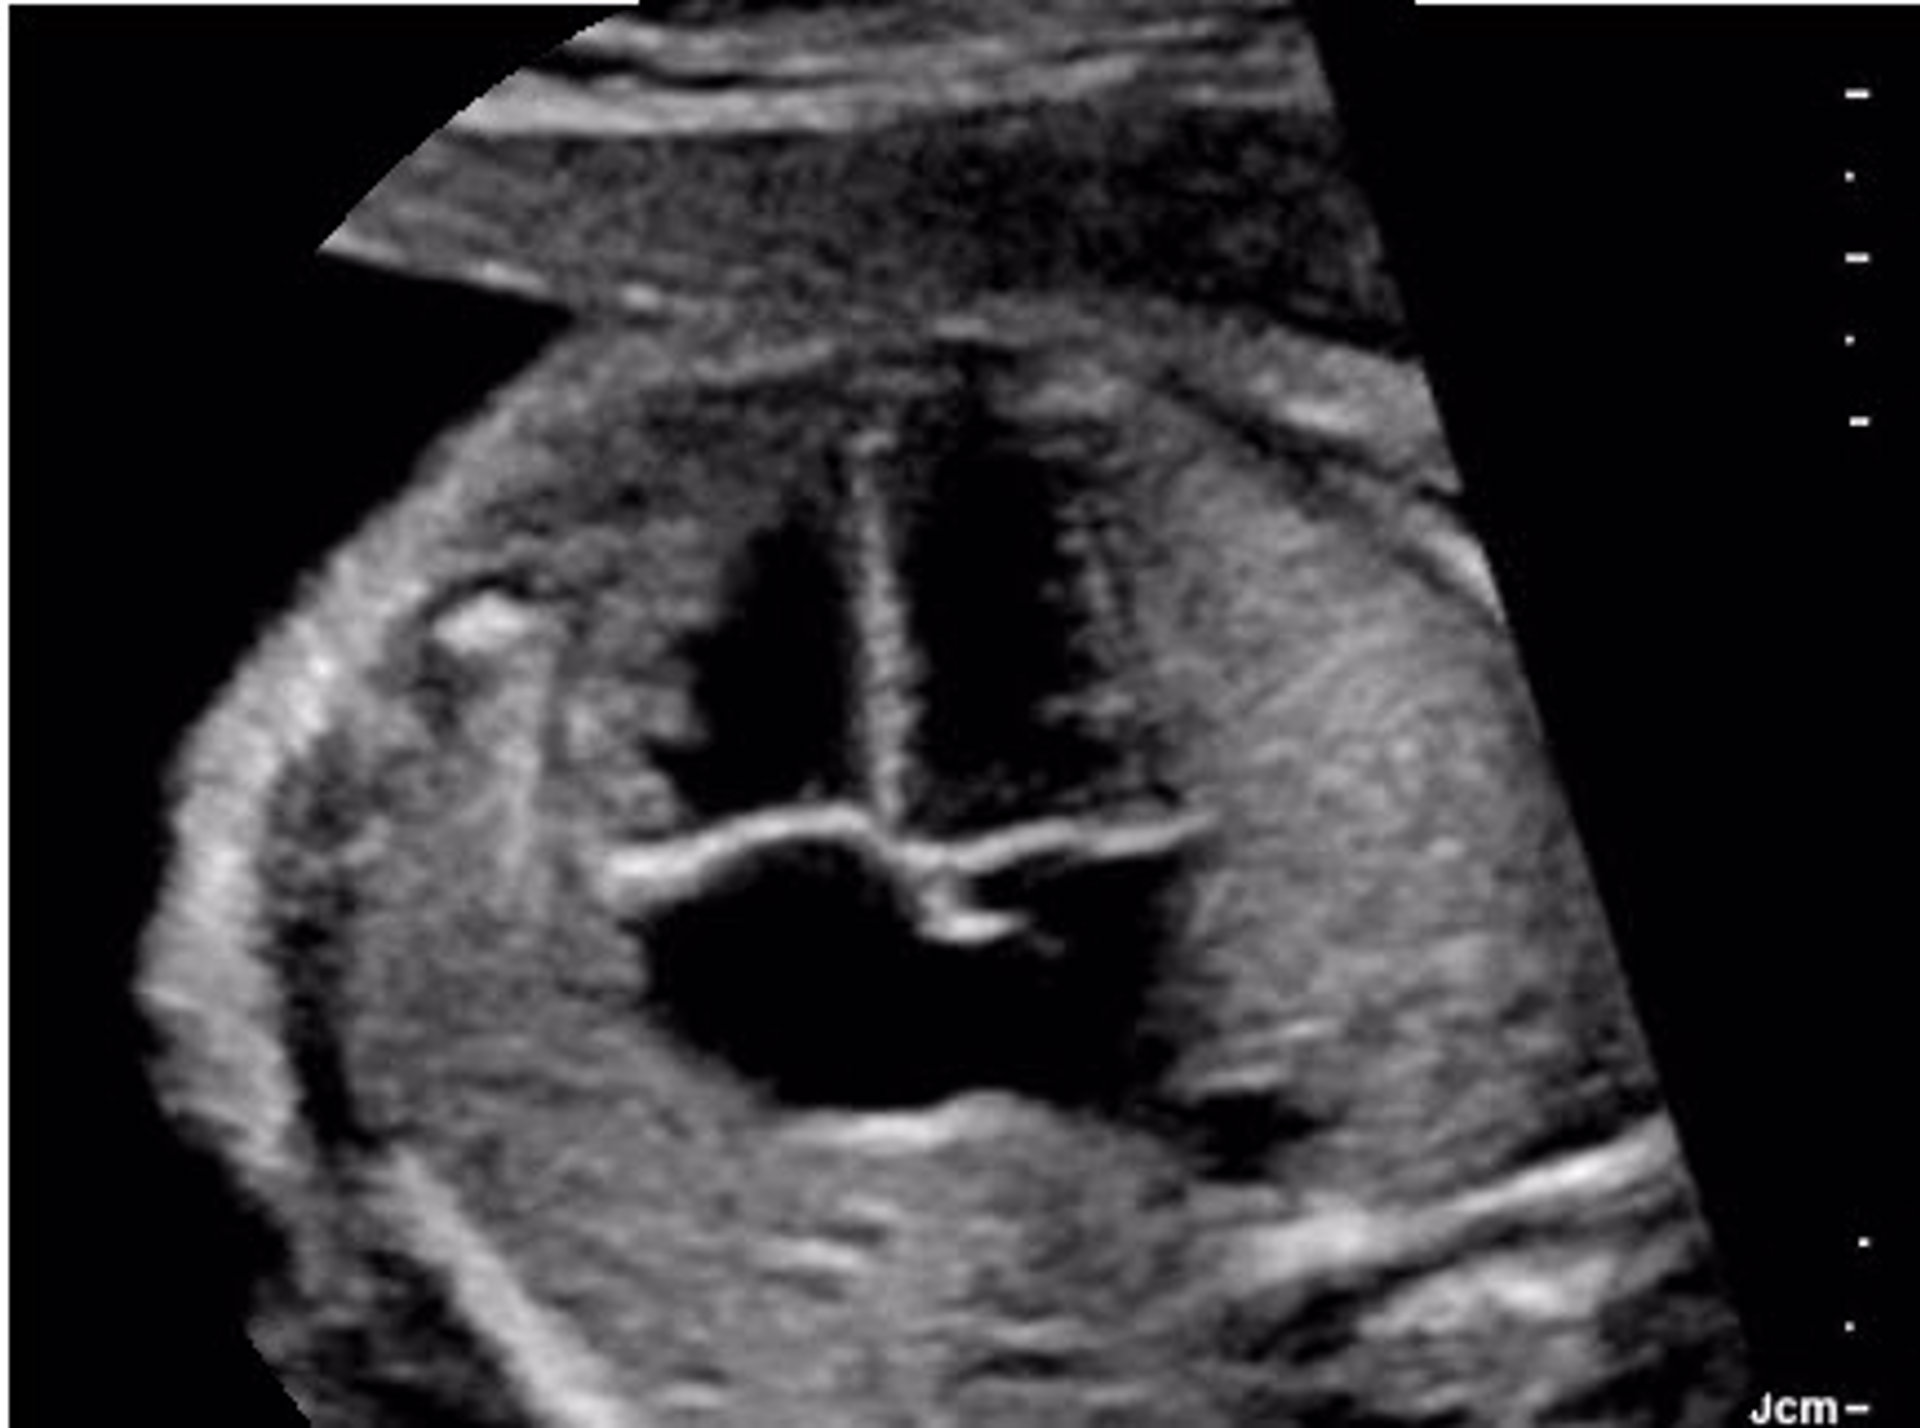

Aufbaukurs: Methoden, Indikationen und Schnittebenen in der fetalen Echokardiografie; Vierkammerblick und große Gefäße: normal und auffällig; Herzfehler: assoziierte Anomalien und Genetik/ Vom Symptom zur Diagnose; Fetaler und perinataler Kreislauf; Dopplersonografie bei fetalen Herzfehlern; Postnatales Management relevanter Herzfehler; Fetale kardiale Funktionsdiagnostik; Langzeitoutcome relevanter Herzfehler; Live-Demonstration, praktischen Übungen in Kleingruppen, Falldemonstrationen und Kasuistiken

Abschlusskurs: Fetales Echo mit 2D und Farb-Doppler; Häufige fetale Herzfehler: warm up; Linksherzanomalien und auffällige große Gefäße; Anomalien des Aortenbogens im Dreigefäßblick; Rechtsherzanomalien; Drehungsanomalien des Herzens; Fetale Arrhythmien; Anomalien der Venen; Frühe fetale Echokardiografie; Leitlinien, Empfehlungen, Dokumentation; 3D am Herzen und Kasuistiken; Schriftliche Prüfung  und Auswertung